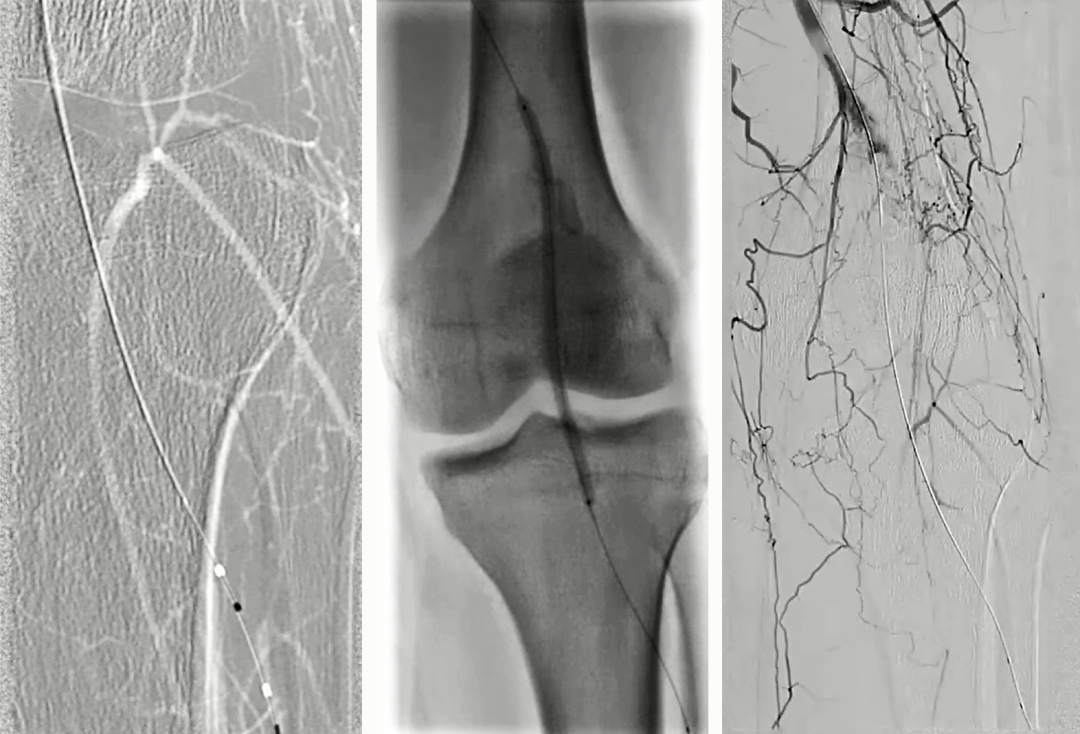

1. 右侧股动脉穿刺,翻山顺行造影显示腘动脉瘤及以远闭塞,仅胫前动脉及腓动脉的近中段显影,踝关节处小腿动脉显影不良,通过侧枝与踝下动脉沟通;

2. 由于顺行无法到达远端真腔,因此从腓动脉逆穿送入V-18导丝,经18支撑导管造影寻找真腔;

3. 在路图指引下支撑导管配合V-18导丝探查腘动脉真腔,V-18导丝经腘动脉跨过假性动脉瘤到达近端股浅动脉真腔,穿管成功,建立股浅动脉至腓动脉通道;